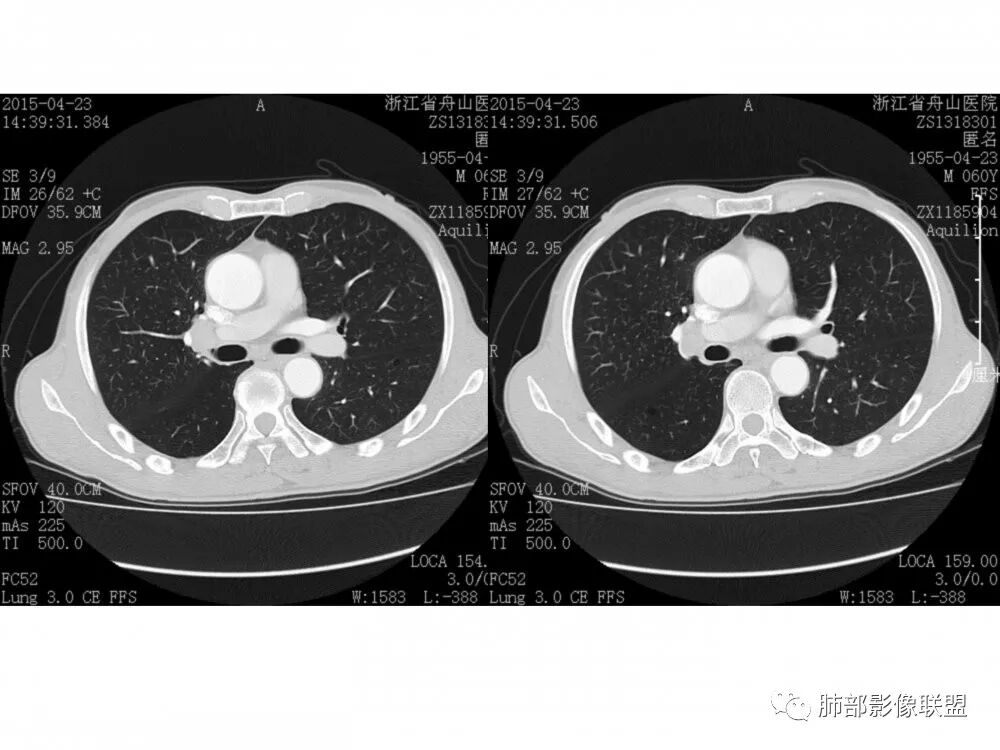

老年男性,60岁,右下肺门肿块,右下支气管粘膜下生长,并堵塞,无明显阻塞性肺炎和肺不张,早期多发淋巴结转移,似不均匀强化。综合看恶性程度高,考虑大细胞癌,一个不支持点,大细胞癌外周多见。

右肺下叶支气管不规则软组织肿块,病灶沿支气管生长,有一定的张力,部分包绕支气管壁,增强病灶内可见中度强化,内部有延迟强化的特点,周围淋巴结增大,诊断恶性病变无疑,远端无明显支气管阻塞,主要考虑粘液表皮癌,腺样囊腺癌,鳞癌之间鉴别,病灶有类似神经源性病变生长方式,腺样囊腺癌,其次考虑鳞癌或粘液表皮癌。

右肺门结节,内见包埋血管,不均匀强化,长轴沿支气管且围绕支气管生长,支气管受压狭窄而未阻塞,肺门及纵隔见肿大淋巴结,老年男性,似有肺气肿背景,考虑恶性肿瘤性病变,首选小细胞肺癌

右中间、右下叶背段支气管管腔内见突向管内的管状软组织影,相邻支气管壁有侵犯,增强有强化,纵隔2R 、4R、10R组淋巴结肿大,增强有强化,未见ct值,常规考虑恶性肿瘤,小细胞癌并同侧纵隔淋巴结转移,鳞癌、类癌街排,建议支气管镜检查。

右肺下叶支气管内新生物,向腔内外生长,黏膜完整,考虑黏膜下,或者气管外来源。淋巴结肿大。考虑恶性,小细胞?间叶来源?建议支气管镜。